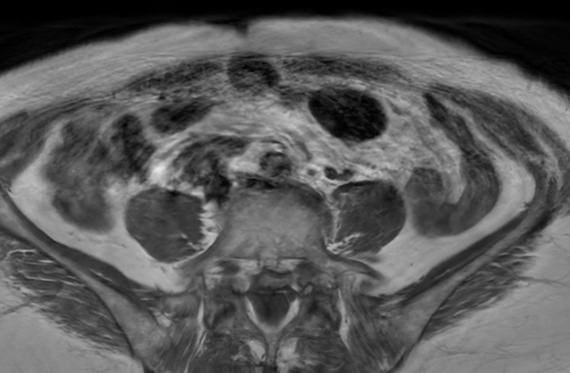

CTA MRI Brain

MRI Brain X-Ray

CT Abdomen MRI Spine

MRI Spine AI Case